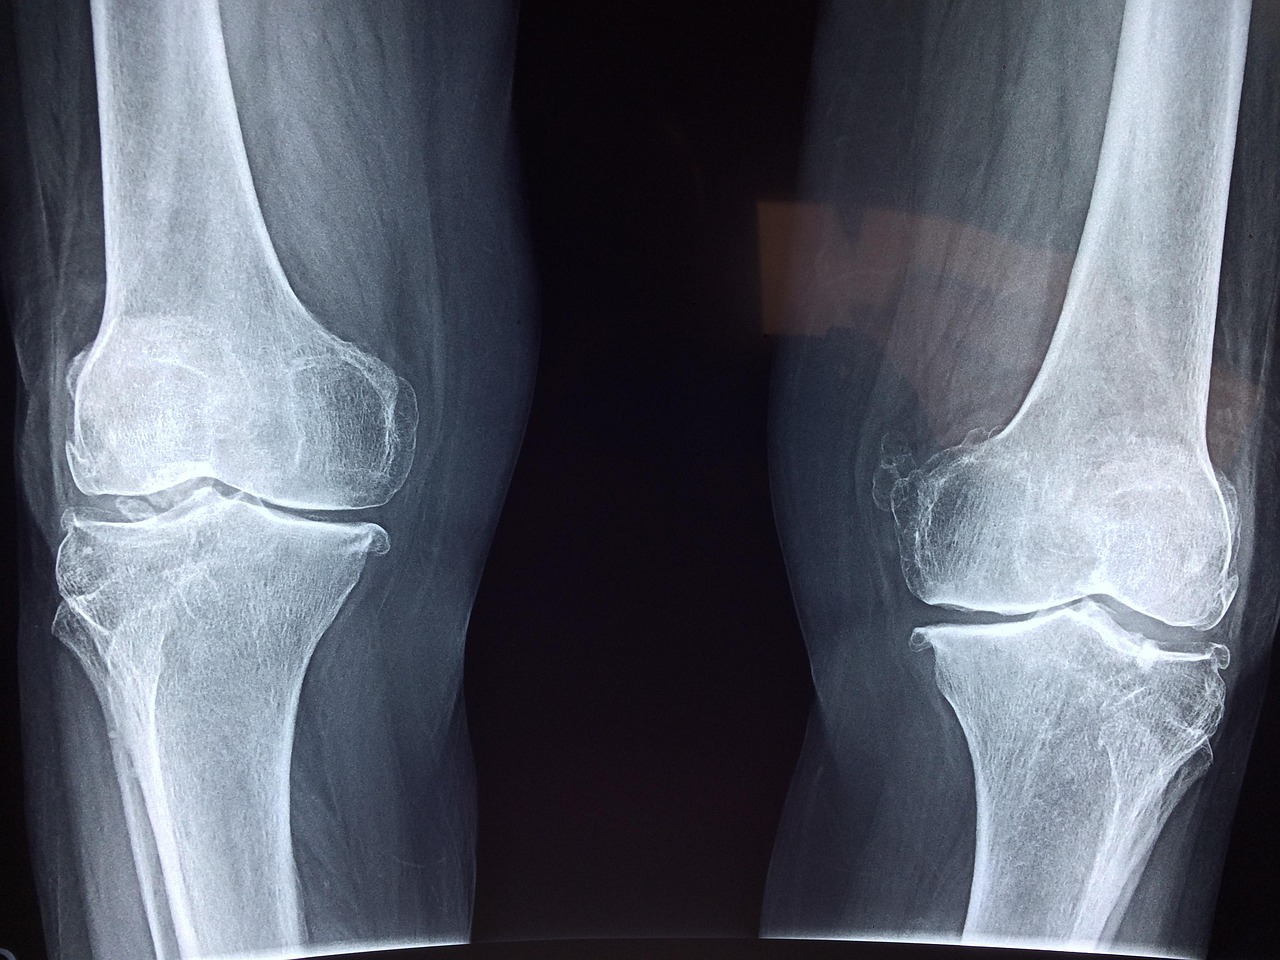

Many people suffer from chronic joint problems that can be influenced by hydration levels. Joint diseases such as osteoarthritis and rheumatoid arthritis can benefit from adequate hydration, emphasizing its importance in managing these conditions. Hydration supports the production of synovial fluid, which is essential for cushioning joints and enhancing mobility. For individuals with arthritis, staying hydrated can alleviate the pain associated with dry joints, which typically results from insufficient lubrication. Medical professionals often recommend increasing water intake in patients diagnosed with chronic joint conditions. Ensuring correct hydration can help reduce inflammation and improve joint function significantly. Furthermore, proper hydration can aid in the management of weight, decreasing the stress placed on joints. Maintaining a healthy weight directly correlates with less joint wear and tear. Arthritis sufferers have reported improvements in joint stiffness and overall comfort by adhering to hydration recommendations. Therefore, it is critical for individuals with chronic joint conditions to prioritize hydration as a cornerstone of an effective management plan. Thoughtful hydration can lead to enhanced quality of life by improving joint function and reducing pain in daily activities.